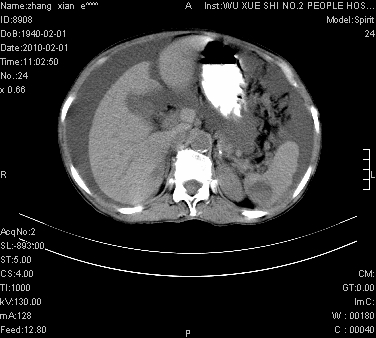

大量腹水,脾脏囊性占位,子宫颈占位,右侧腹股沟淋巴结肿大,建议+c,先查妇科。

大量腹水,脾囊肿可能性大,建议增强

腹盆腔大量积液,子宫增大,子宫颈增大外形不规则,内见低密度影,膀胱后壁显示不清,右腹股沟肿大淋巴结,脾脏囊性占位,子宫颈占位,子宫颈癌?建议增强。

子宫、宫颈占位?转移性腹水?肝性腹水?脾脏囊性占位,囊肿?血管瘤?淋巴瘤?

大量腹水,右肾、脾囊肿可能性大          考虑左侧附件区占位,建议增强